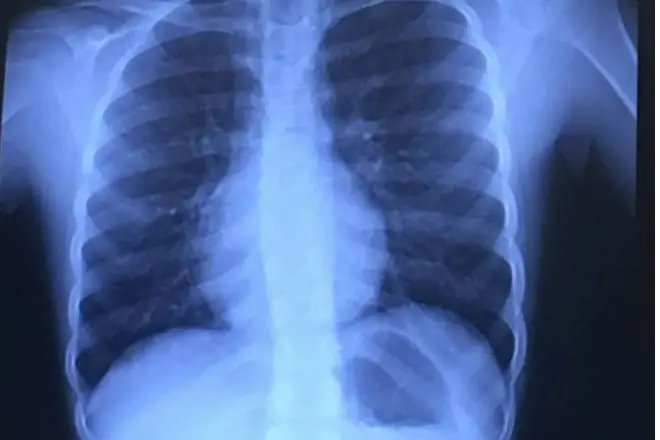

Когда Келли доставила Бриттон в отделение неотложной помощи, ее вскоре перевели в Техасскую детскую больницу, где рентген показал небольшую часть спиннера, застрявшую в ее трахее.